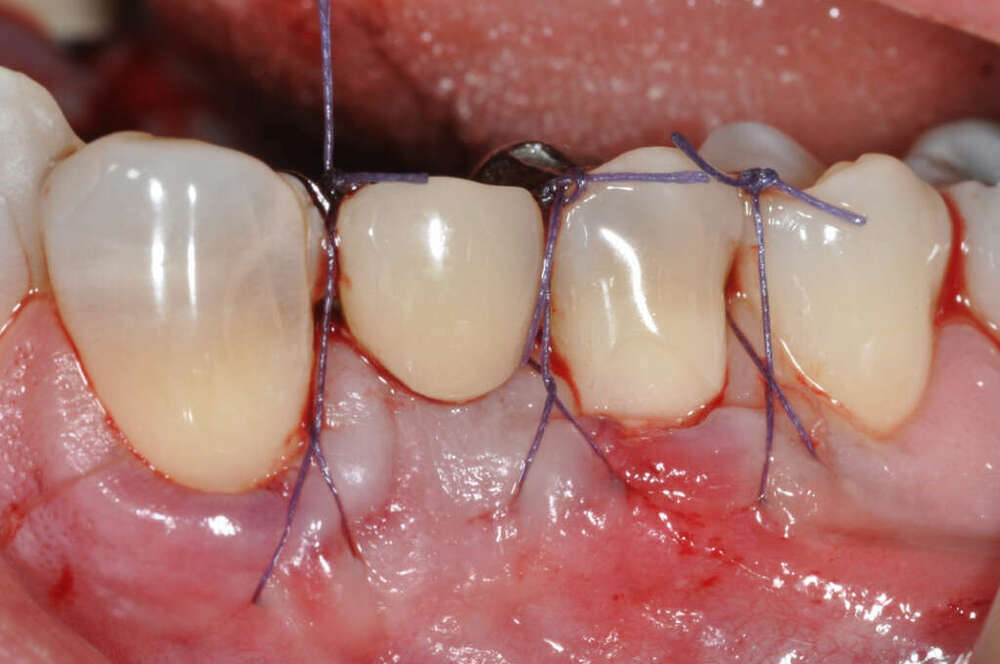

Cas cliniques : greffe gingivale à visée esthétique au Cabinet Dentaire du Docteur Picard, à Rouen.

Exemples de cas : cas 1

Exemples de cas : cas 2